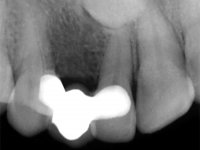

Female patient, 43 years old, non-smoker. Showed an edentulous space in the upper right canine area, resulting from tooth 1.3 impaction. The space had a mesio-distal diameter reduced to the normal size of the upper canine. This is consistent with the presence in the arch of the deciduous canine up to two years ago). Orthopantomography allows clearly view of tooth 1.3 impaction.The patient has a thick gingival phenotype and tolerable oral hygiene.